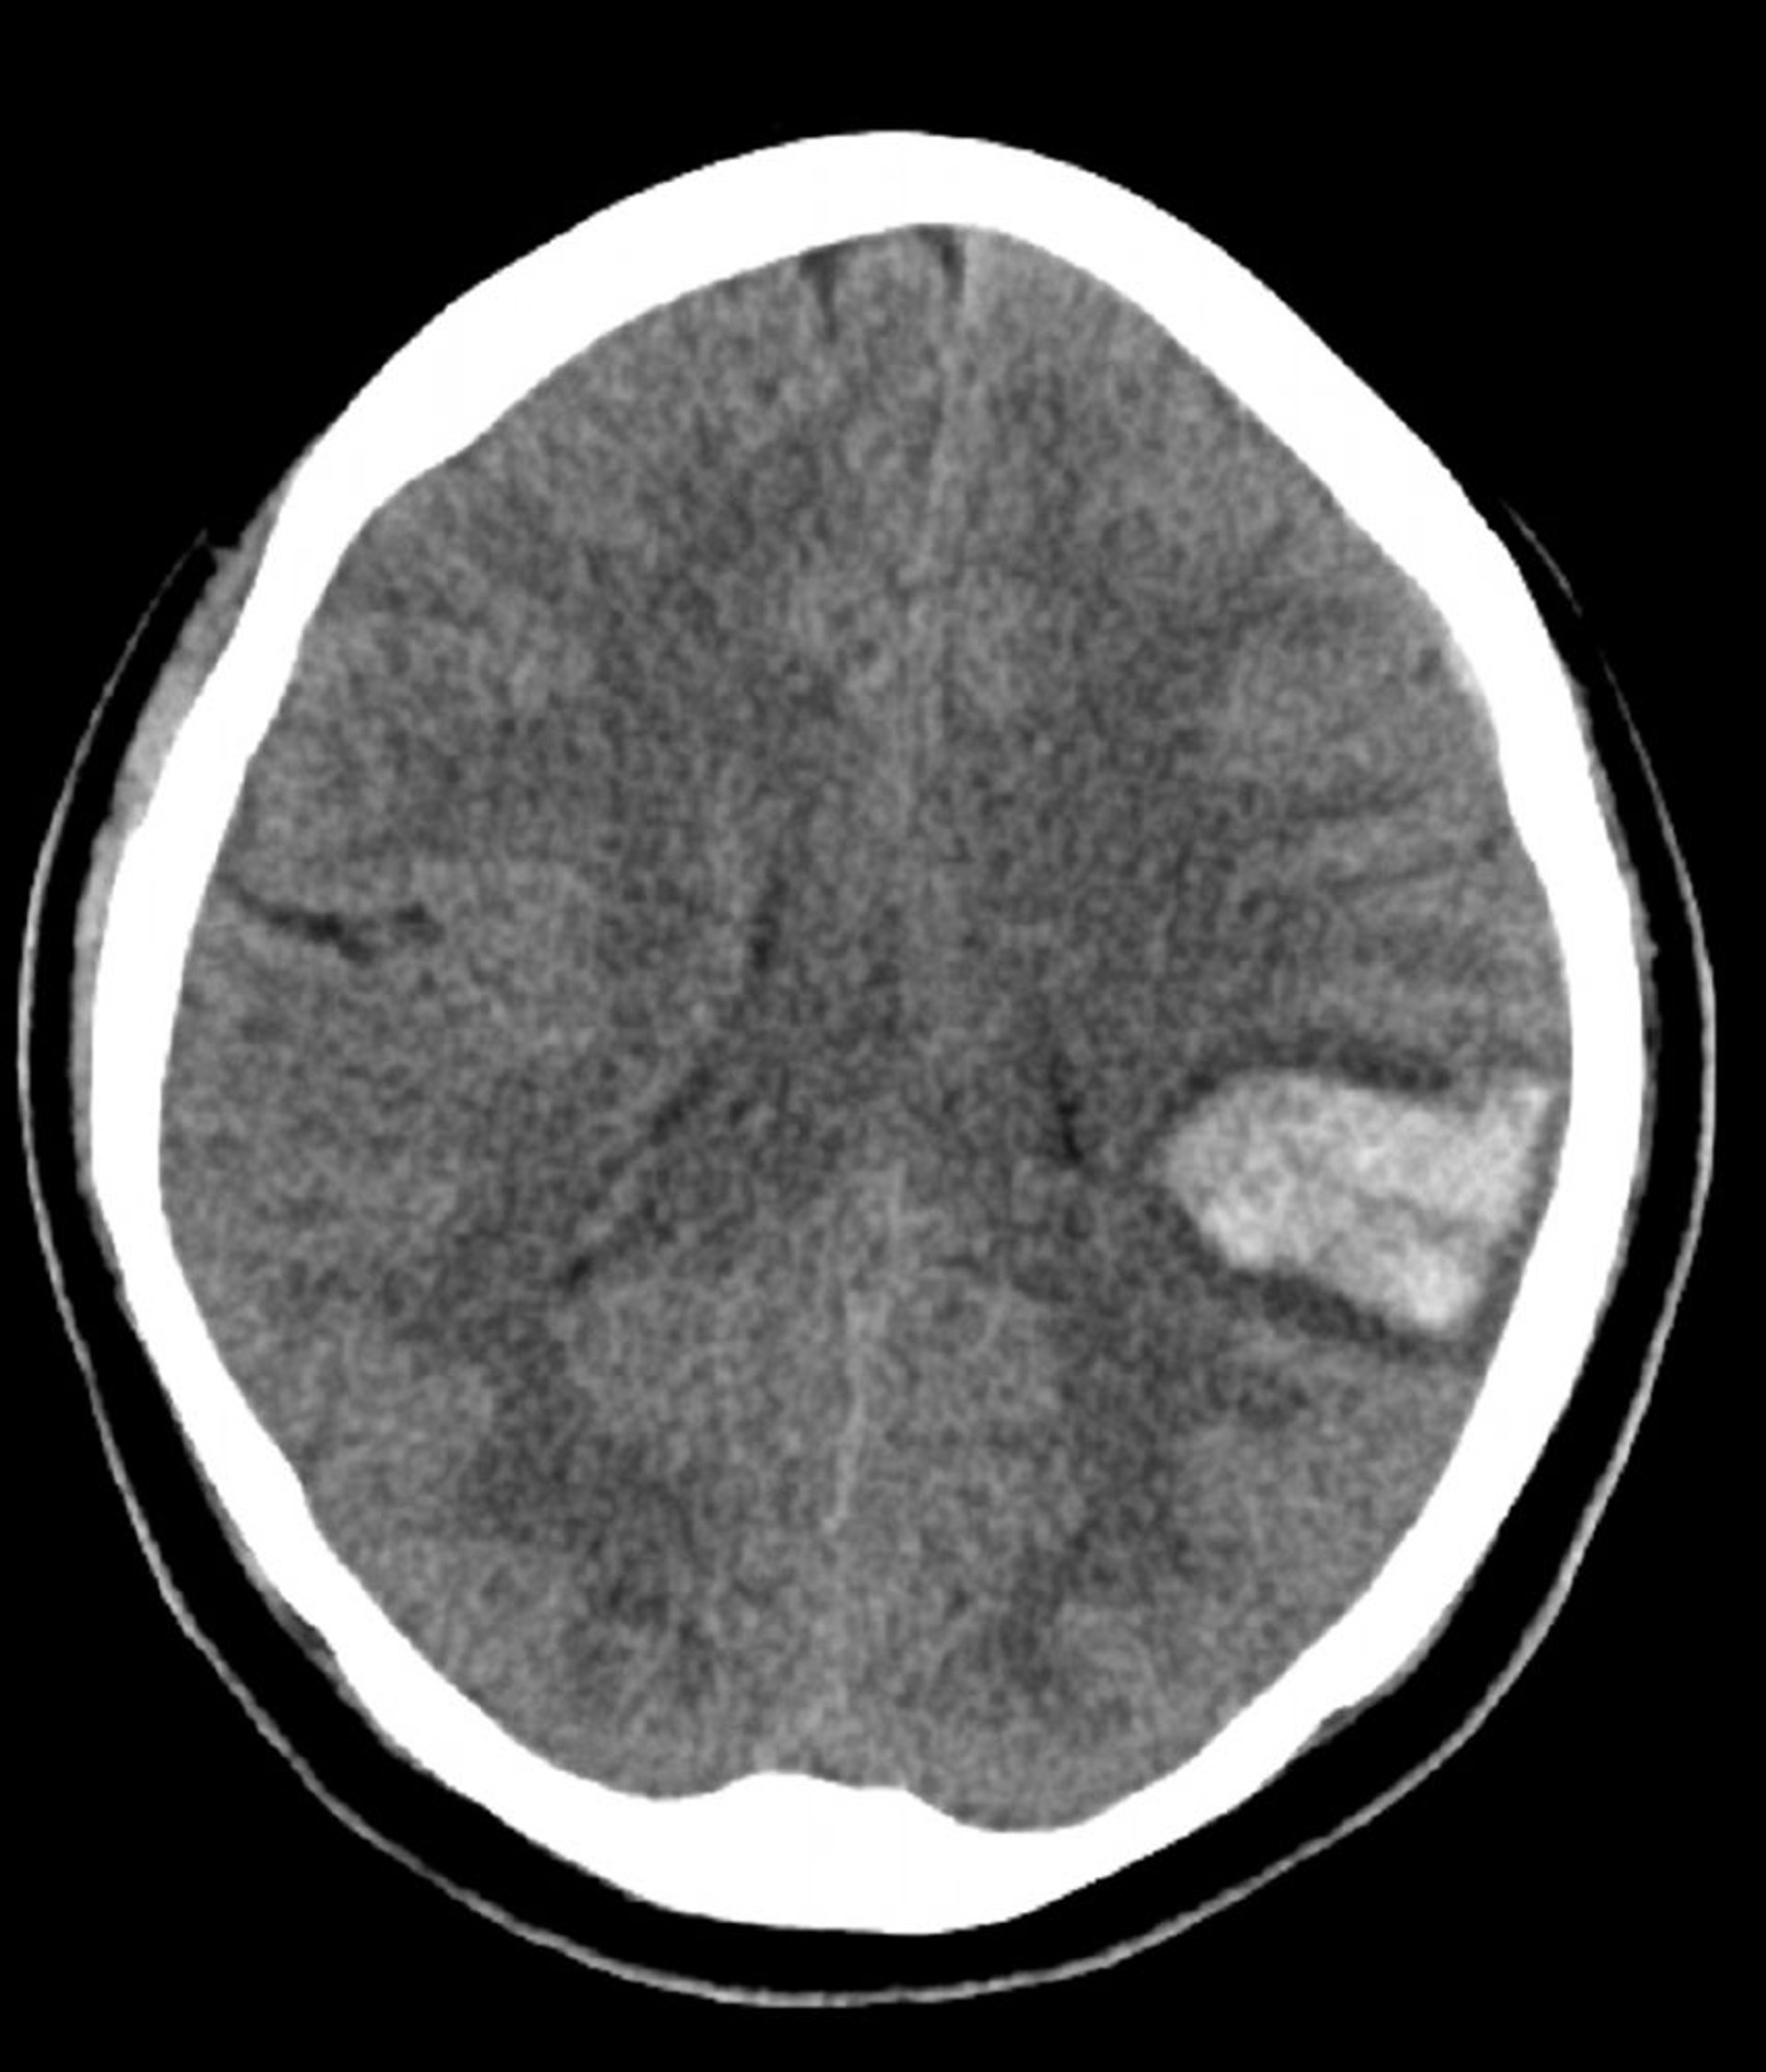

Intrazerebrale Blutung

Die erhöhte Dichte im linken Gehirn auf diesem nicht kontrastverstärkten CT ist konsistent mit einer intrazerebralen Blutung.